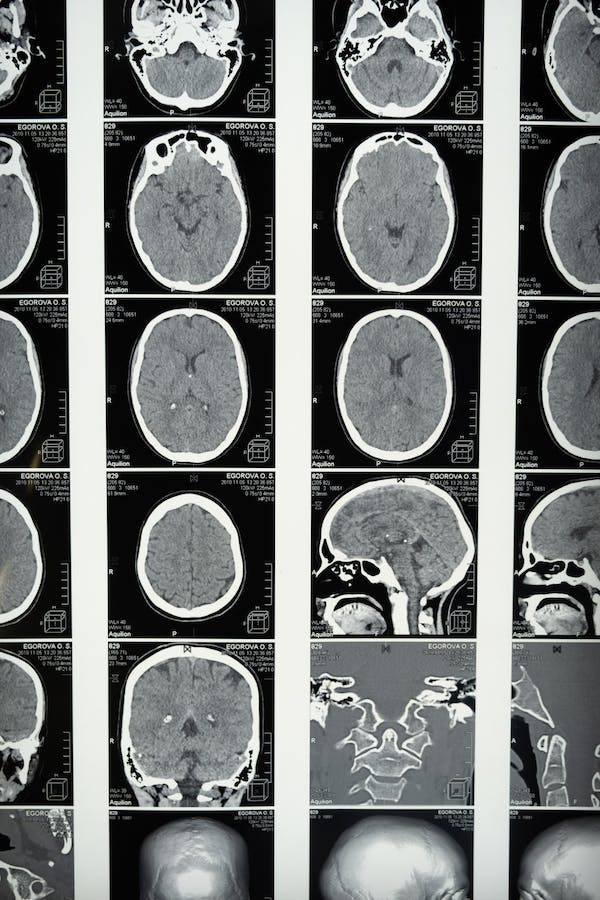

El deterioro cognitivo es una característica fundamental de la esquizofrenia. Entre los factores probables en la persistencia de los déficits cognitivos en este trastorno se encuentran los cambios en el tejido cerebral a lo largo del tiempo.

El papel de la microestructura de la materia blanca cerebral para mantener la velocidad de procesamiento y otras medidas cognitivas ha sido reportado en diversas investigaciones. Así, la velocidad de procesamiento y la memoria de trabajo dependen de operaciones de redes neuronales a gran escala y larga distancia.

Lo anterior es respaldado por fibras axonales neuronales mielinizadas. De esta forma, las limitaciones cognitivas en las personas con esquizofrenia coinciden con déficits en la microestructura de la materia blanca cerebral.

La rehabilitación cognitiva ha mostrado ser efectiva en personas con esquizofrenia. Así, incluso se han observado efectos en la disminución de la pérdida de materia gris en las etapas iniciales de la afección. Sin embargo, esto dependerá de la reserva cognitiva previa del sujeto y sus problemáticas particulares, siendo este un abordaje personalizado.